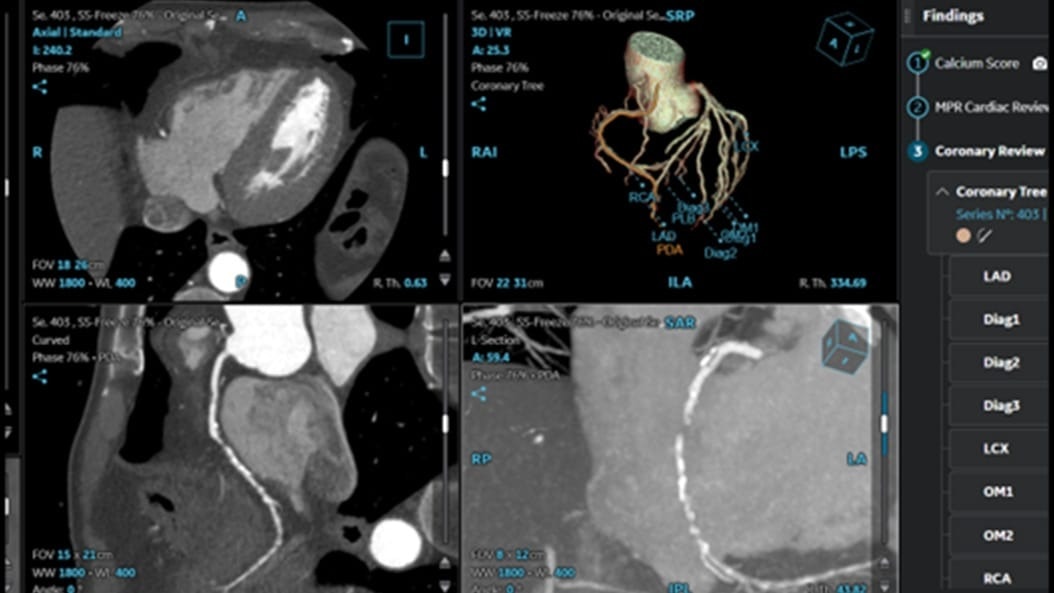

CardiQ Suite

An integrated suite of CT Cardiac post-processing tools, built for automation and workflow efficiency.

Consistency

>90% concordance with CACS‑DRS classification grouping⁵

Identification

>95% correct identification of the presence of coronary artery calcifications⁵

Labeling

>90% accurately labeled coronary artery territories⁵